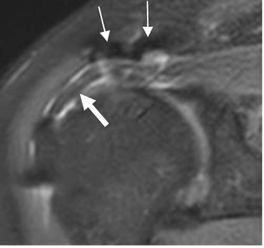

Fig 159. Cambios PostQx.

RM coronal en STIR. Cambios PostQx en la articulación acromioclavicular, que producen artefactos. (Flechas delgadas). Signos de tendinitis del supraespinoso, el cual está adelgazado y rodeado por líquido. (Flecha gruesa).